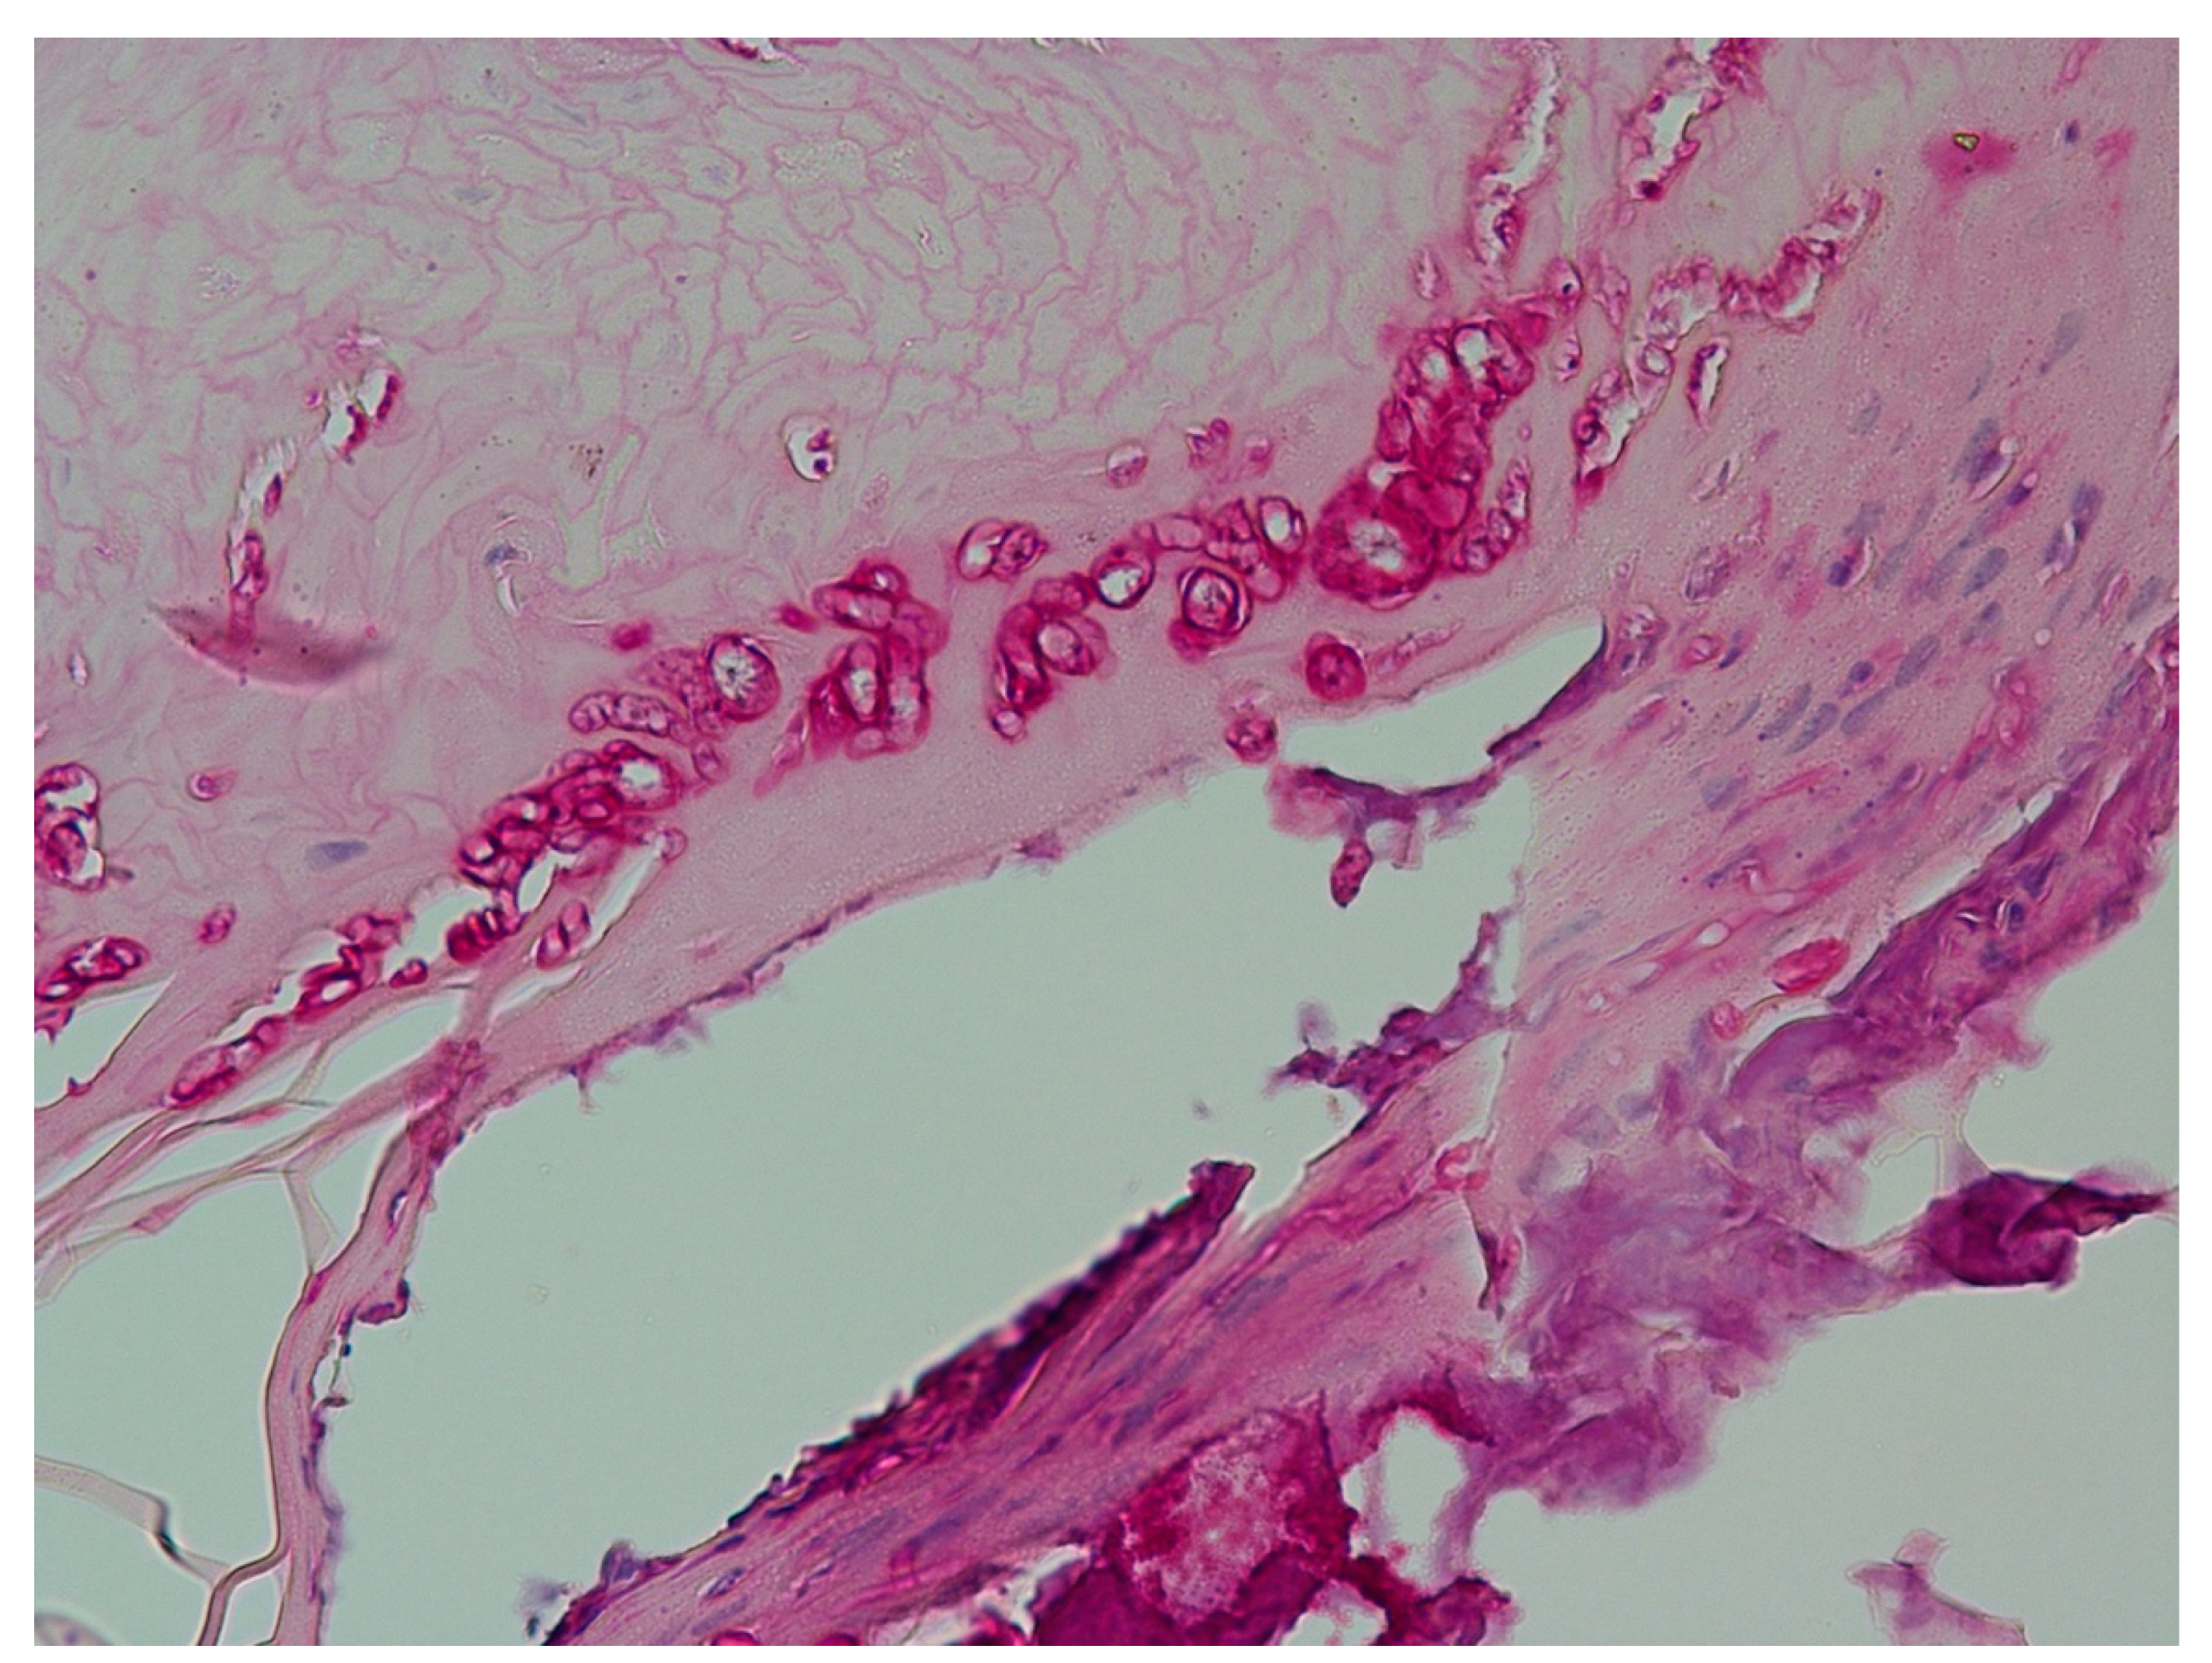

| Histopathology (PAS, Grocott) | Differentiation of type of fungal infection, high yield of positives, differentiation between invasive onychomycosis and colonization, differential diagnoses possible. | No species identification. |